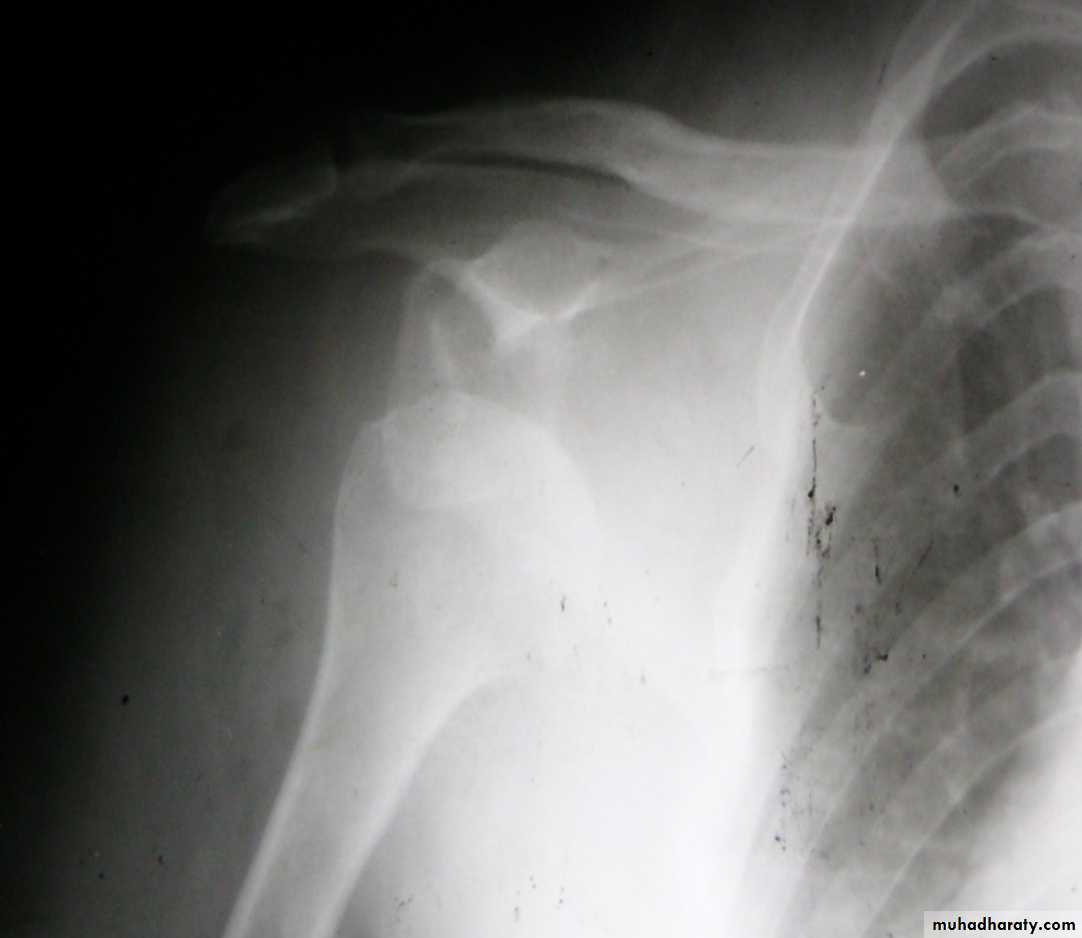

Slide 31. What diagnostic features can you see?2. What is the diagnosis?.